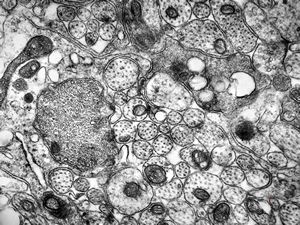

F,50y. | progressive multifocal leukoencephalopathy- viral particles in a glial cell